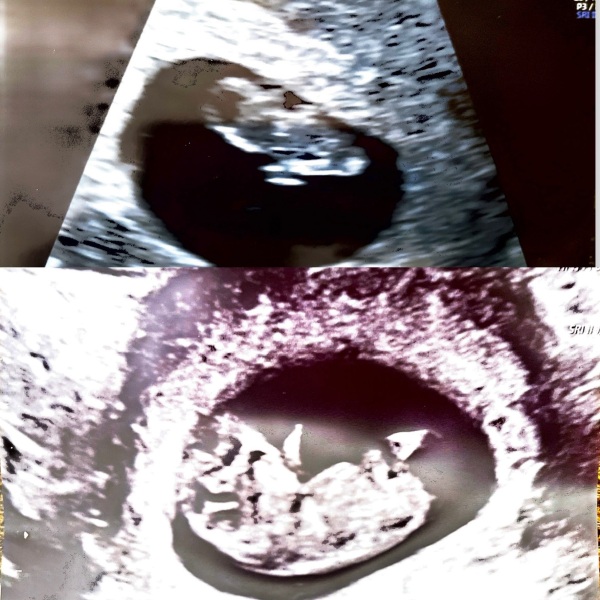

Top was a scan at about 7 weeks (measured 7.5) and then bottom was a scan at 9+3. Had no plans for a second scan but after awful awful cramping decided to get one for piece of mind. Was interesting to see how much it had grown!

This is my 9 weeks 4 gummy bear i saw on Thursday :) it was wriggling away and waving at me, couldn't believe how mobile they are at this age!